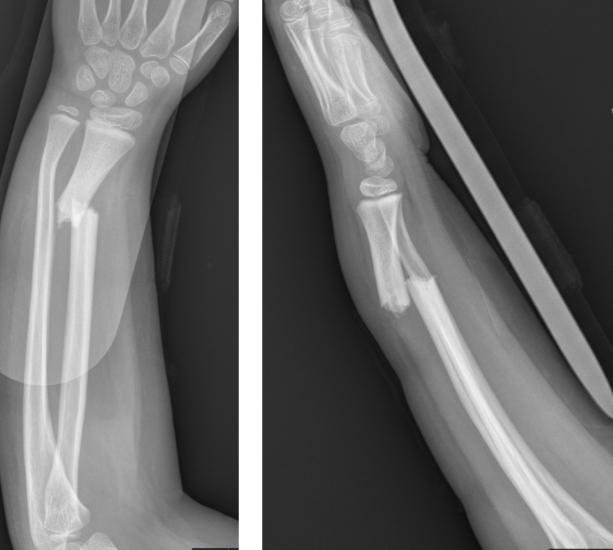

Fractura de radio y cúbito en niño, el tratamiento correcto !!

¿Tu hijo ha sufrido una fractura de radio y/o cúbito.

Quieres saber si es grave o no y como se debe solucionar??